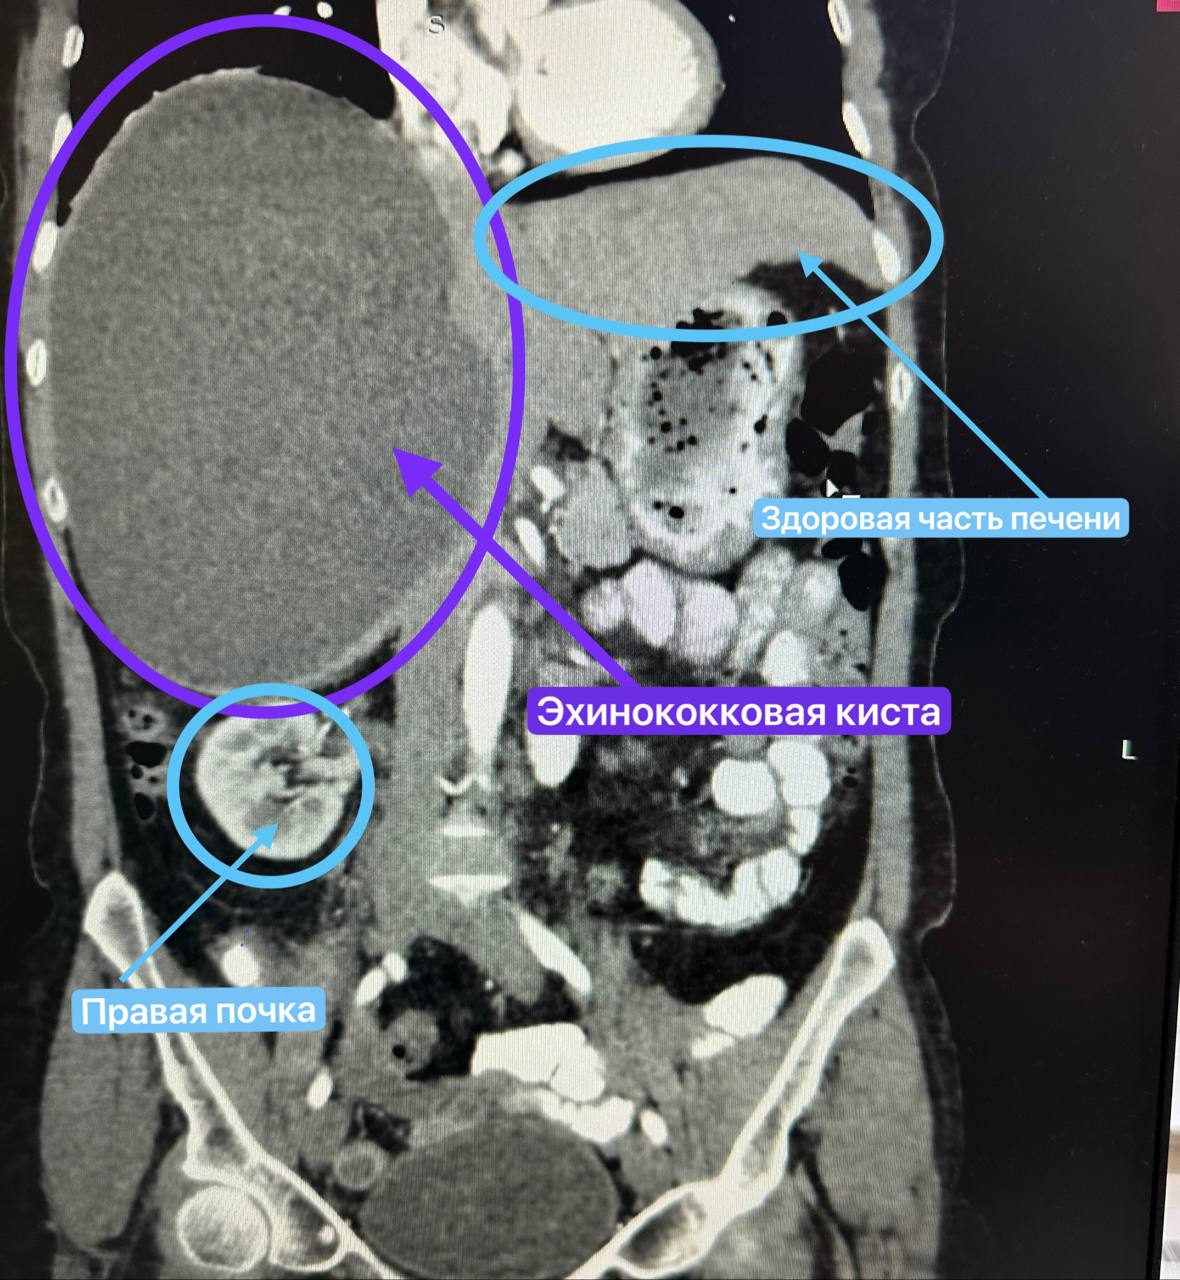

В августе женщину перевели в хирургическое отделение №2 РКБ, где команда опытных специалистов провела операцию. Киста достигала 20 на 12 сантиметров и весила около двух с половиной килограммов. Образование настолько разрослось, что сдавливало соседние органы, а правая почка сместилась с привычного места. После успешной операции женщина чувствует себя хорошо и постепенно готовится к выписке, отмечают врачи.